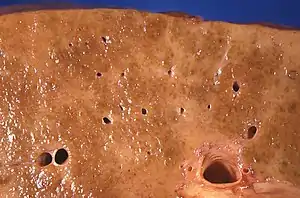

Macroscopically, the liver is initially enlarged, but with the progression of the disease, it becomes smaller. Its surface is irregular, the consistency is firm, and the color is often yellow (if associated with steatosis). Depending on the size of the nodules, there are three macroscopic types: micronodular, macronodular, and mixed cirrhosis. In the micronodular form (Laennec's cirrhosis or portal cirrhosis), regenerating nodules are under 3 mm. In macronodular cirrhosis (post-necrotic cirrhosis), the nodules are larger than 3 mm. Mixed cirrhosis consists of nodules of different sizes.[37]

Micronodular cirrhosis, with diffuse areas of pallor.

Micronodular cirrhosis, with diffuse areas of pallor..jpg.webp) Pale macronodules of cirrhosis.

Pale macronodules of cirrhosis. Cirrhosis leading to hepatocellular carcinoma (autopsy specimen)

Cirrhosis leading to hepatocellular carcinoma (autopsy specimen)